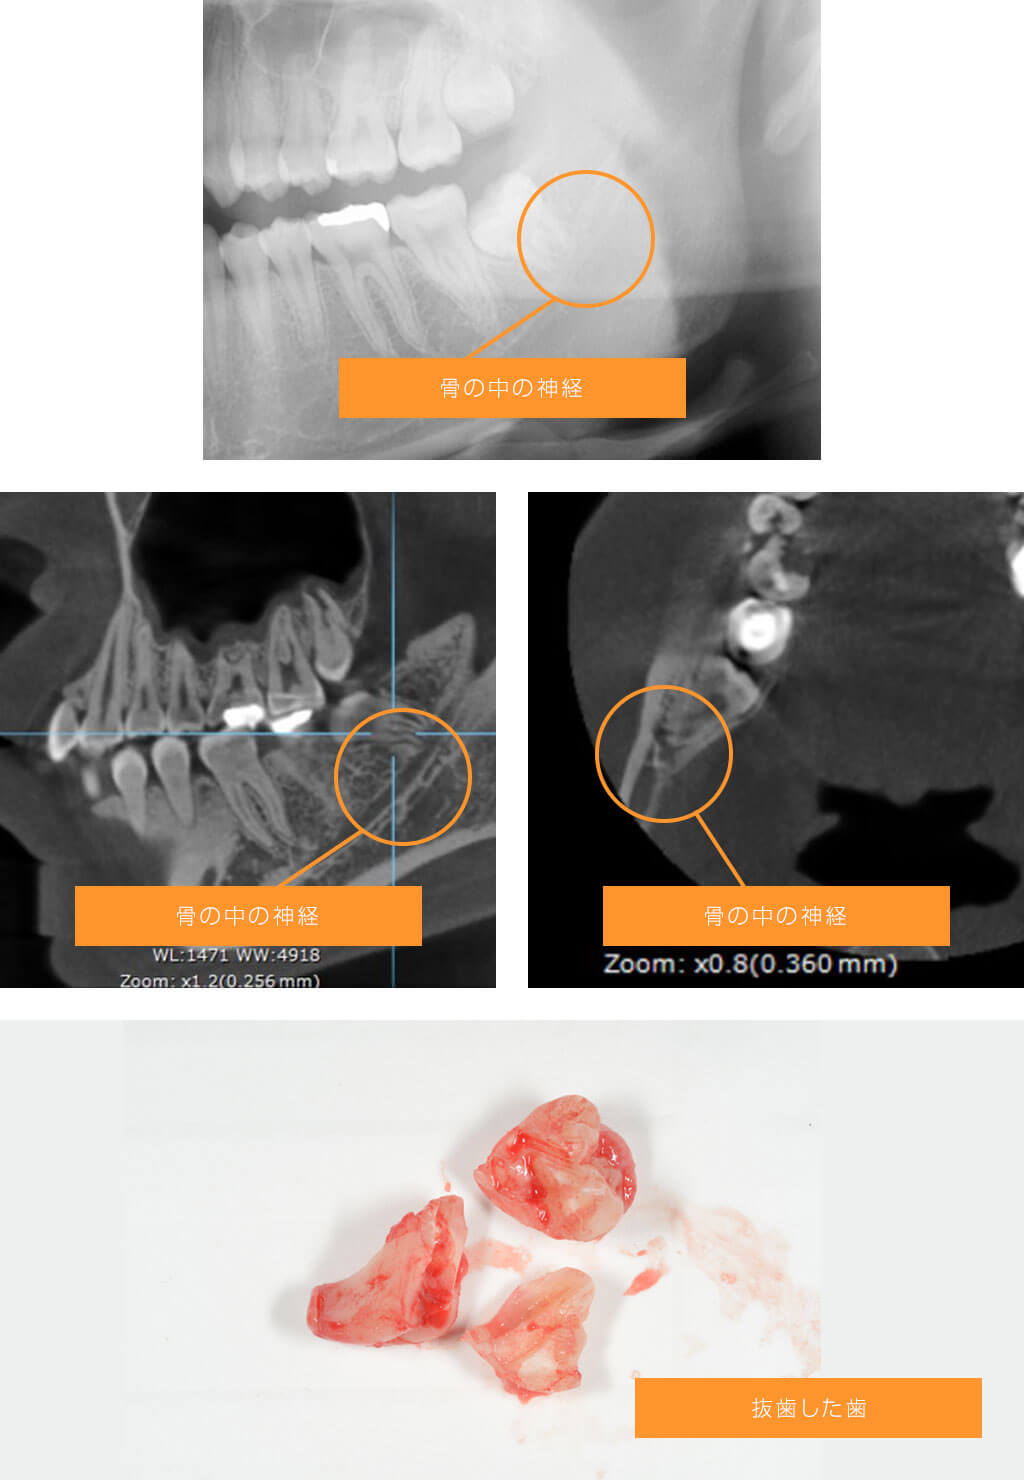

症例1 下顎の神経と左下の親知らずが近接している場合

正元のコメント

下顎の親知らずでは根の先に神経(下唇の感覚を司る神経)が近接していることがあります。通常のX線写真では根と神経の位置関係が分かりにくく、CTを撮影することで位置関係を把握することができます。この方の場合、パノラマX線写真で親知らずの根の先に神経が近かったため、CTを撮影しました。CTでも親知らずの根の先に神経が近接していました。リスクを説明した上、抜歯に同意が得られたので、CTで得た情報から神経に負担を与えないように骨を削る場所や抜く方向を工夫して抜歯しました。術後の唇の感覚障害は生じず抜歯できました。

患者さまの感想

病院の口腔外科では入院しての抜歯を説明されたので、歯科医院で抜歯できないかと色々調べてしょうげん歯科医院を受診しました。抜歯後腫れた程度で何事もなく終わり、とても満足しています。

処置時間と費用

処置時間:約45分(麻酔時間含め)

費用:約9,000円(パノラマ、CT費用含む)

リスクと副作用

術後に腫れや痛みが生じ、時に痛みがひどい場合があります。この症例の場合うまくいきましたが、神経と近接する親知らずの抜歯では術後に下唇、まれに舌の感覚障害が生じる場合があります。